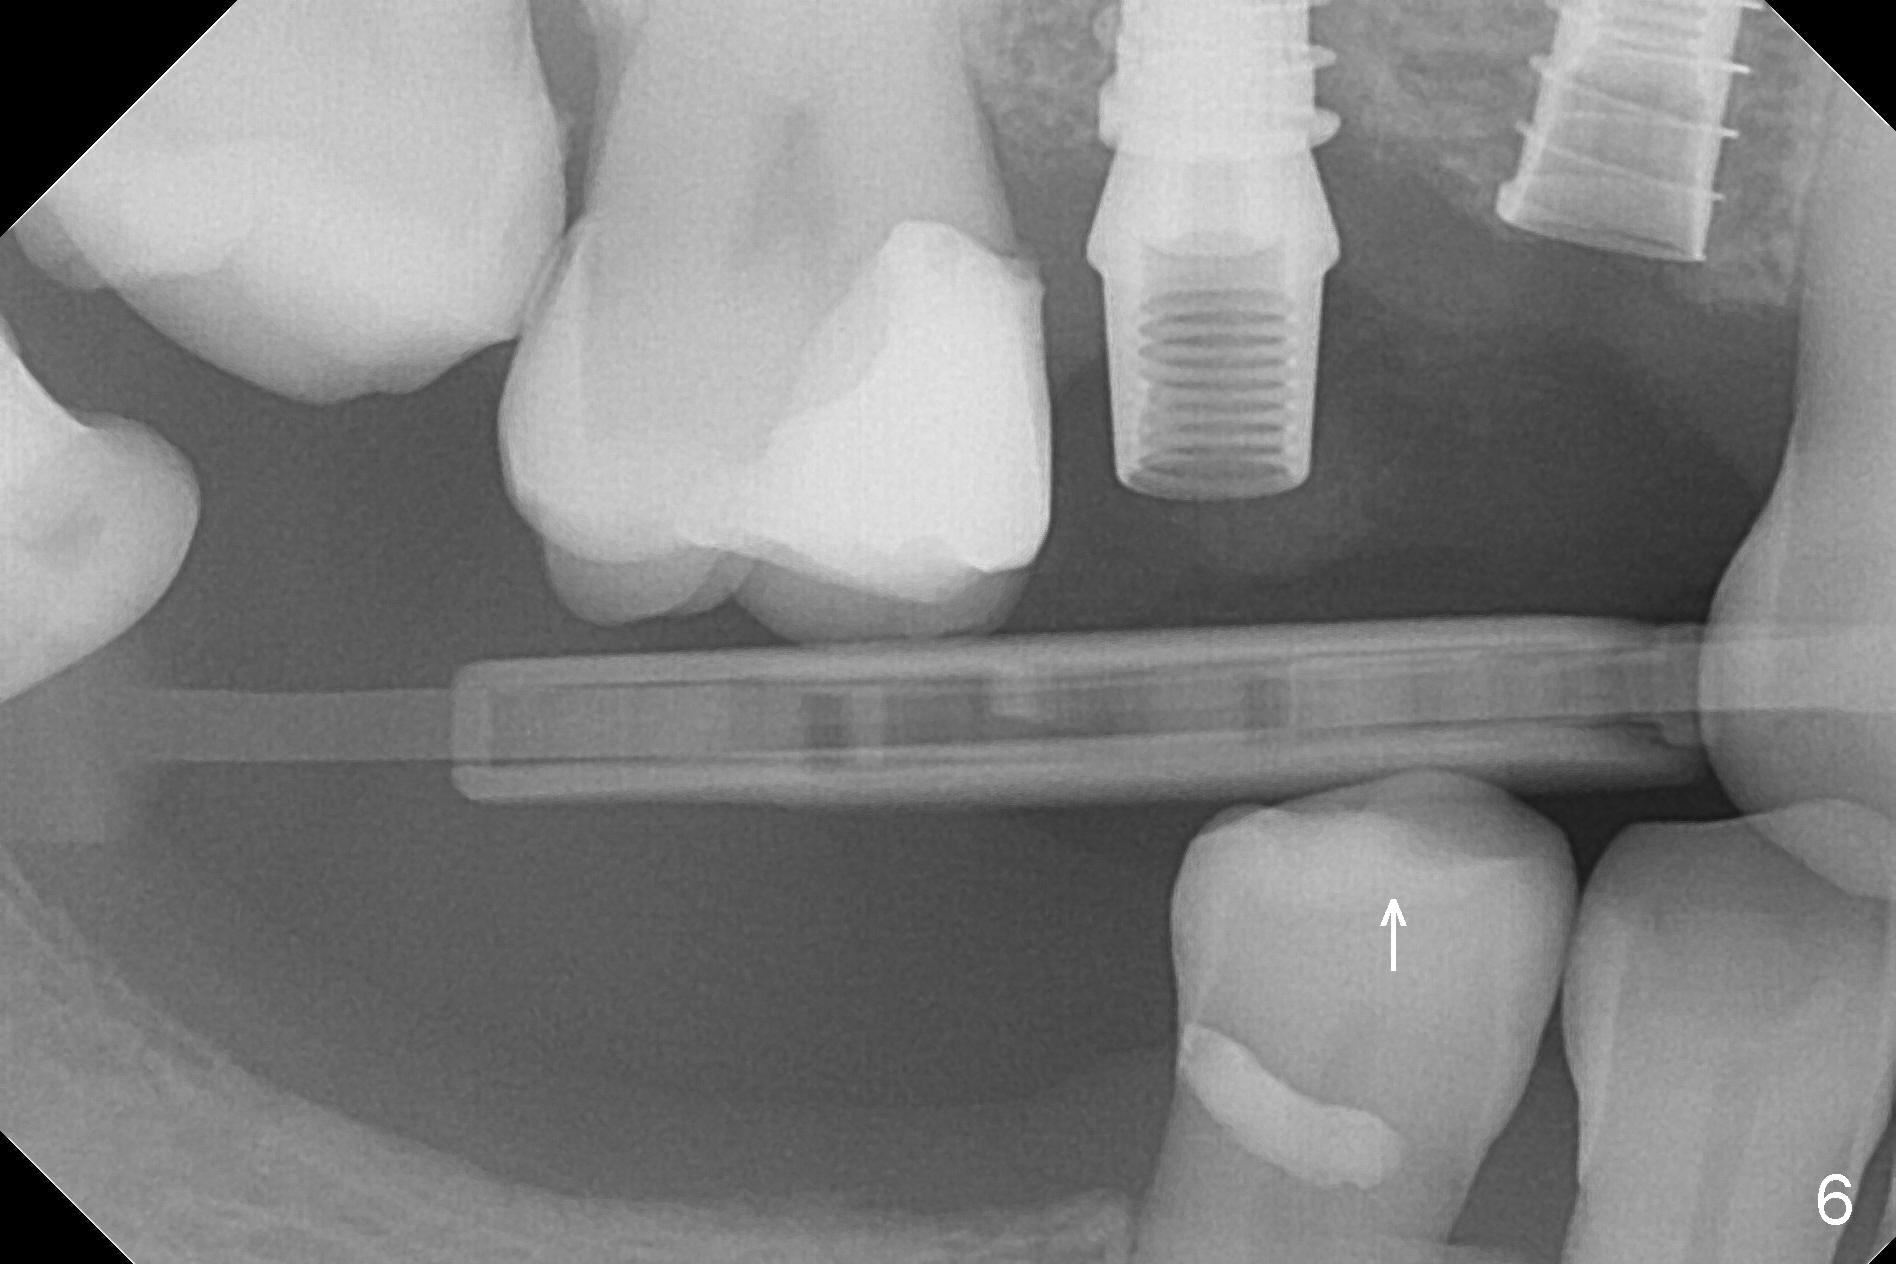

At the healed site (#5), insertion torque of a 4x11 mm implant is >50 Ncm (Fig.4). Because of supraeruption of the tooth #28 (Fig.6 arrow), a healing abutment (4x2 mm) is placed at #5 (data not shown), while a pair abutment (4.5x4(2) mm) is placed at #4 (Fig.4,6). In fact a splinted provisional is placed at #4 and 5 with a low occlusal table. There is no apparent bone loss 1 years 5 months postop (Fig.7). In fact the implants either perforate the palaatal or buccal (B) plate, as revealed by CBCT (1 year 6 months postop, immediately post cementation, Fig.8,9). It appears necessary to have guided surgery and smaller implant in the narrow ridge.